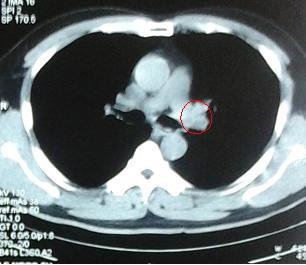

Hình 2. Hình ảnh chụp cắt lớp vi tính ngày 13/10/2014, khối u kích thước 4x4cm (vòng tròn vàng), tràn dịch màng phổi trái (mũi tên)

Sau 3 đợt hóa trị + thuốc chống hủy xương + P32, bệnh nhân được chụp cắt lớp vi tính lồng ngực nhằm mục đích đánh giá đáp ứng sau điều trị. Trên hình ảnh chụp cắt lớp vi tính lồng ngực cho thấy: nhu mô phổi trái có khối dạng hình tam giác, ngấm thuốc đều sau tiêm, kích thước 23x11mm không có tràn dịch màng phổi trái, không có hạch to trung thất.

Hình 5. Hình ảnh chụp cắt lớp vi tính lồng ngực của bệnh nhân sau 3 đợt điều trị hóa chất (vòng tròn đỏ là tổn thương còn lại)